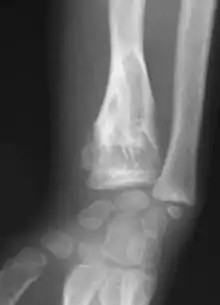

Abnormal bone growth such as shortening or thickening and deformity may be observed in patients of Ollier disease. These bone lesions are visible at birth using radiography but are usually not screened or examined for until clinical manifestations present during early childhood. However, some patients may exhibit no signs of any symptoms.[1] One study found thirteen to be the mean age of diagnosis in patients with Ollier disease. In an X-ray, there would normally be the presence of several homogeneous lesions of an oval or elongated shape with bone edges that are slightly thickened.[3] With age, these lesions may calcify and appear as diffusely minute spots or stippled. Fan-like septations or streaks would be indicative of the presence of several enchondromas. Early detection and consistent and repeated monitoring is important in order to prevent and treat any potential bone neoplasms.